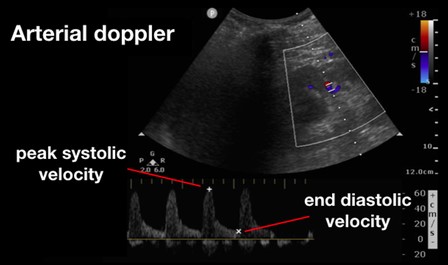

Intra-renal doppler exams, on the other hand, require a lateral view of each kidney to obtain a classic renal view (Figures 4 and 5). Use color Doppler to identify the interlobar vessels that lie beside the medullary pyramids. If not readily appreciable on initial views, fan the probe or alter alignment until an appropriate color flow can be identified. After the vessels are identified, switch to pulsed wave Doppler and place the gate over the interlobar vessels, allowing for identification of the arterial and venous waveforms. From these images you should be able to evaluate the renal artery resistive index (RRI) and renal vein pulsatility waveform.

Figure 4. Renal Arterial Resistive Index (RI) 10

(Reproduced with permission from Rola, Spiegel, and Haycock)

Beyond the liver, the renal artery and vein play an important role in the assessment for venous congestion and fluid overload. To accomplish this, doppler evaluation typically aims to determine blood flow within the interlobular or arcuate vessels within the renal parenchyma. As both the artery and vein run together, the renal arterial and venous waveforms are usually obtained simultaneously. For the artery, a pulsatile waveform is located as seen in Figure 4. The renal resistive index (RRI) can then be calculated by taking the systolic peak velocity minus the end-diastolic velocity over the peak systolic velocity (RRI = [Vs-Vd]/Vs). When this value is greater than 0.7, it is considered to be pathologic, and is concerning for decreased renal perfusion via a decrease in diastolic arterial blood flow. As this value approaches 1, the diastolic arterial blood flow is absent. This finding, however, is nonspecific for venous congestion itself, although impairments in arterial flow can provide a window into venous congestion, especially within cardiac patients.